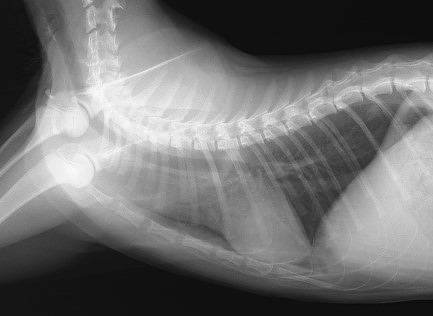

咳をする若い猫ちゃんの胸部レントゲン写真です。大きな異常は認められないですが、

拡大して肺の後ろ側をよく見ると、白いポッチのような病変(赤矢印)がいくつか確認できます。これは気管支パターンと言って、気管が腫れていることを示す所見です。この子は非常に軽い気管支パターンでしたが、喘息の治療をしたところ症状が改善しています。猫の喘息は体質が関与していると見られ、時々再発を繰り返しますが、治療への反応がよい子は普段の生活に支障がない程度に回復してゆきます。